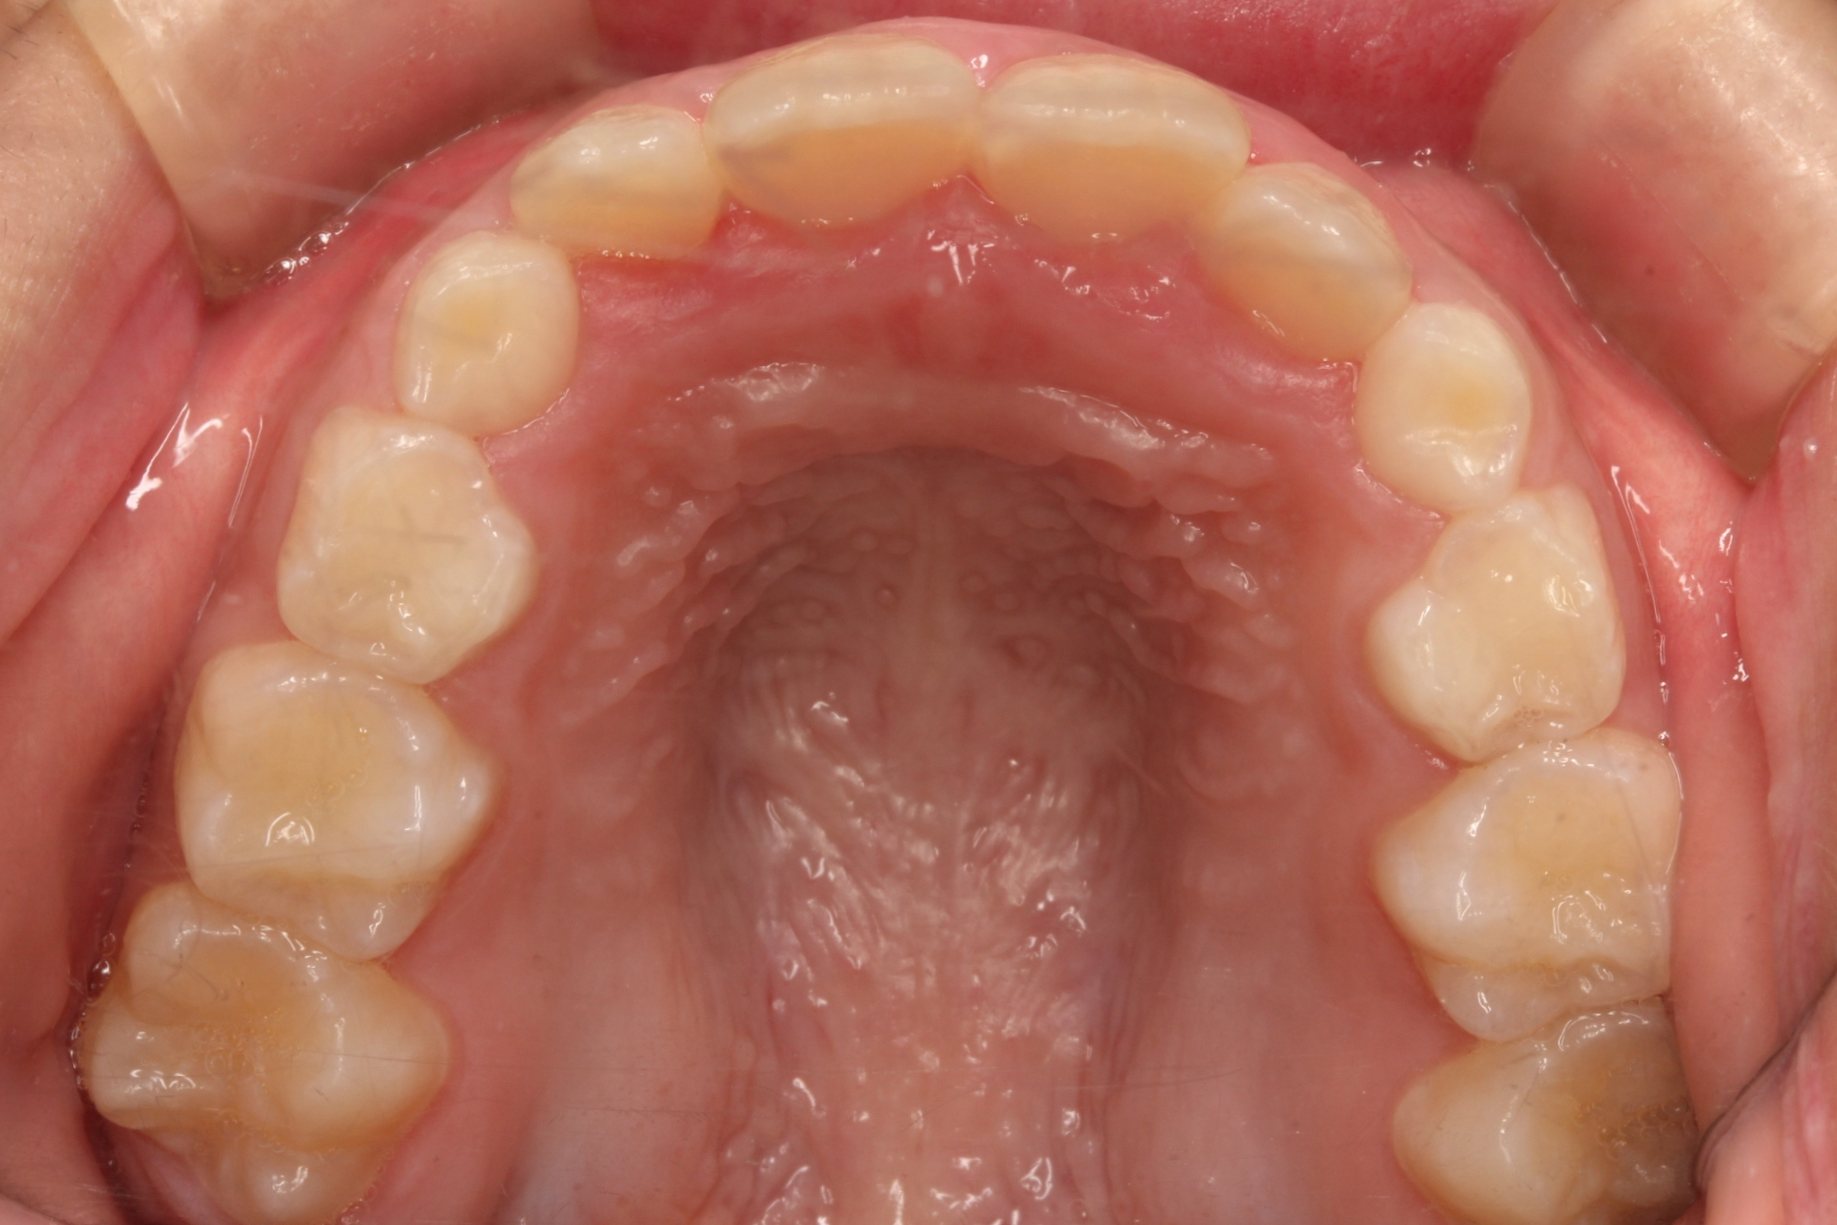

矯正術前:上顎

| 主訴 | 下の前歯のがたつきが気になる |

| 治療内容 | 患者様は、下の前歯のがたつきを気にされており、矯正検査後叢生Ⅰ級と診断いたしました |